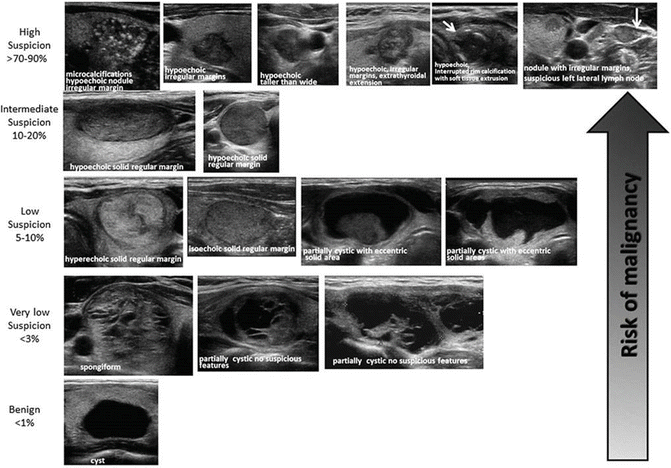

Suspicious sonographic findings of the thyroid

A

• Hypoechoic

• Microcalcifications

• Extrathyroidal extensions/Infiltrative margins

• Irregular margins

• Taller than wide

• Lymph node involvement